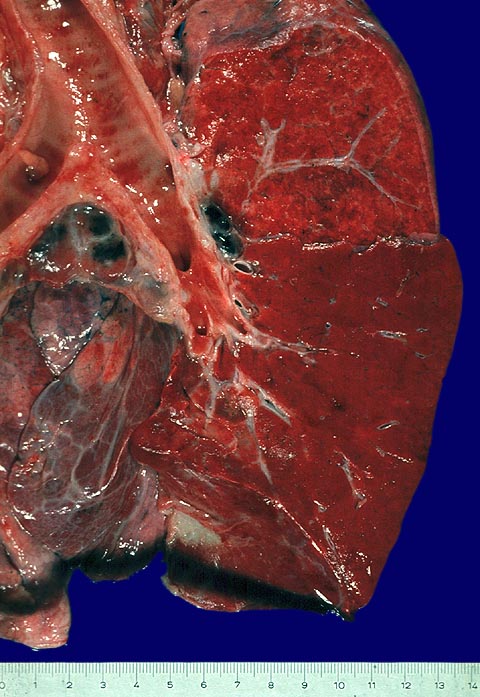

Die meisten bakteriellen und bakteriell superinfizierten viralen Pneumonien verlaufen als alveoläre Pneumonien. Der Ausbreitung nach werden sie unterteilt in lobäre Pneumonien mit gleichmässigem Befall grösserer Lungenabschnitte und Herdpneumonien, bei denen sich multiple Herde entwickeln. Eine Lobärpneumonie tritt auf, wenn die Erreger die Alveolarräume so ausgedehnt und rasch befallen, daß sie erst vor anatomischen Grenzen (z.B. Lappenspalt) Halt machen.

Aufgrund der heute rasch einsetzenden antibiotischen Therapie bei klinischer Diagnose einer Pneumonie, kommen die charakteristischen Stadien der Lobärpneumonie nur noch selten zur Beobachtung. Die unbehandelte Lobärpneumonie verläuft in vier Stadien:

Anschoppung (1. -2. Tag)

Rote Hepatisation (2.-3. Tag)

Graue Hepatisation (4.-6. Tag)

Gelbe Hepatisation (7.-8. Tag)